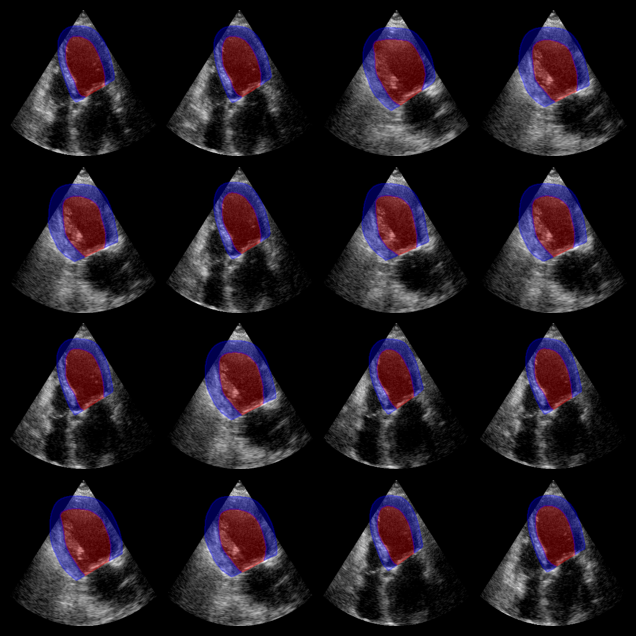

Augmented CAMUS segmentation results:

Red: left ventricle mask. Blue: myocardium mask.

Augmented CAMUS Segmentation Output

First we test the Augmented CAMUS nnU-Net model, which segments both the left ventricle and myocardium (2 labels). The model expects input in NCHW format (batch, channels, height, width).

# Visualization: show both LV (label 1) and myocardium (label 2)

for ax, mask in zip(axes, masks_camus):

# LV: label 1, Myocardium: label 2

plot_shape_from_mask(ax, mask == 1, color="red", alpha=0.3)

plot_shape_from_mask(ax, mask == 2, color="blue", alpha=0.3)